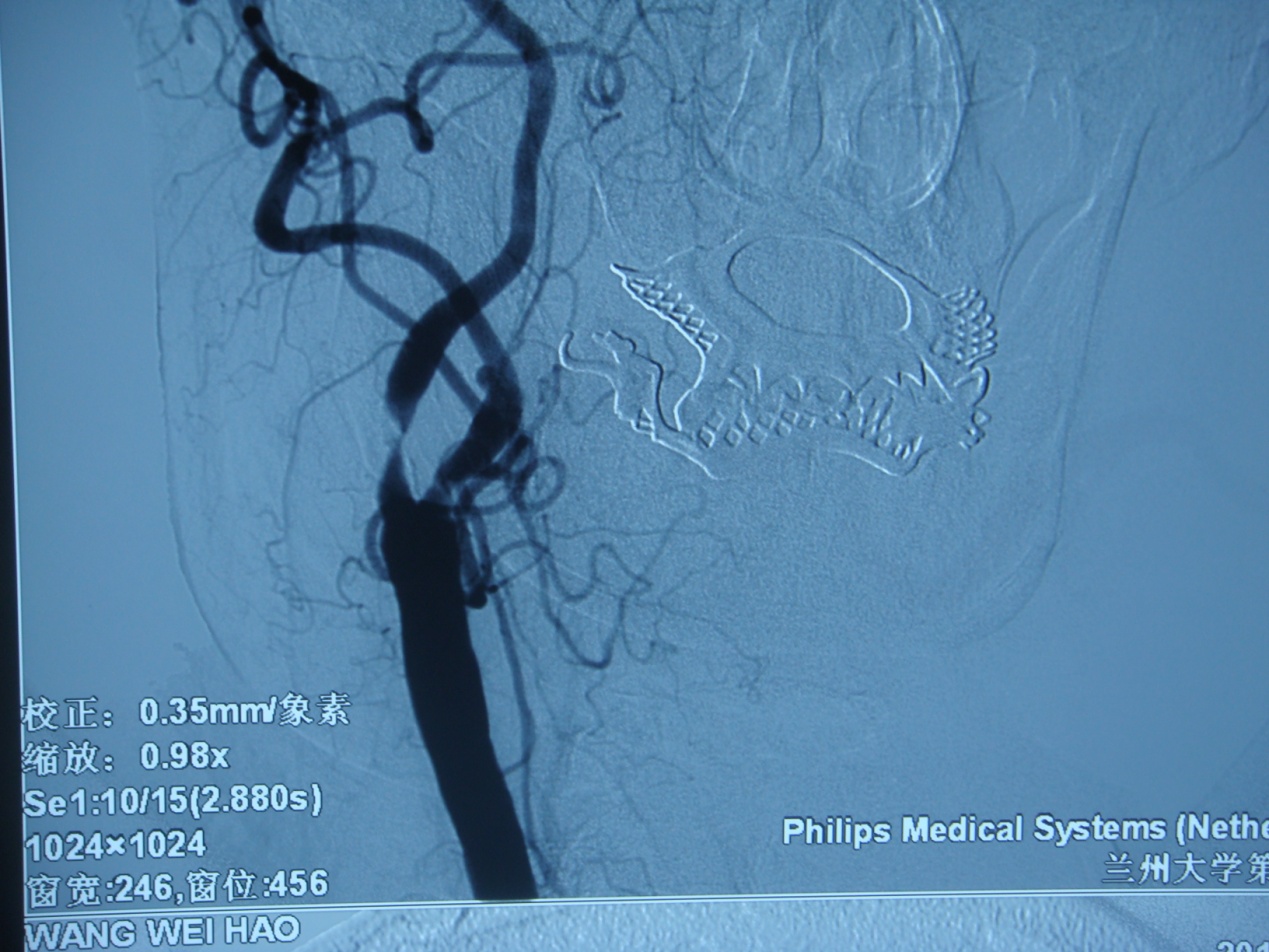

术前DSA显示右侧颈内动脉狭窄99%。